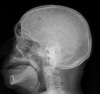

27

What is the term for the radiographic sign that is characteristic of multiple myeloma in the skull?

raindrop skull

28

What is the first radiographic sign of multiple myeloma?

generalized osteopenia

What is on your list of differential diagnoses for a 55 year old patient with an aggressive radiographic lesion, and raindrop skull?

A

1. Multiple myeloma

2. mets

3. lymphoma

What would prompt you to put multiple myeloma at the top of your list of differential diagnoses?

- lab findings (M spike) - raindrop skull